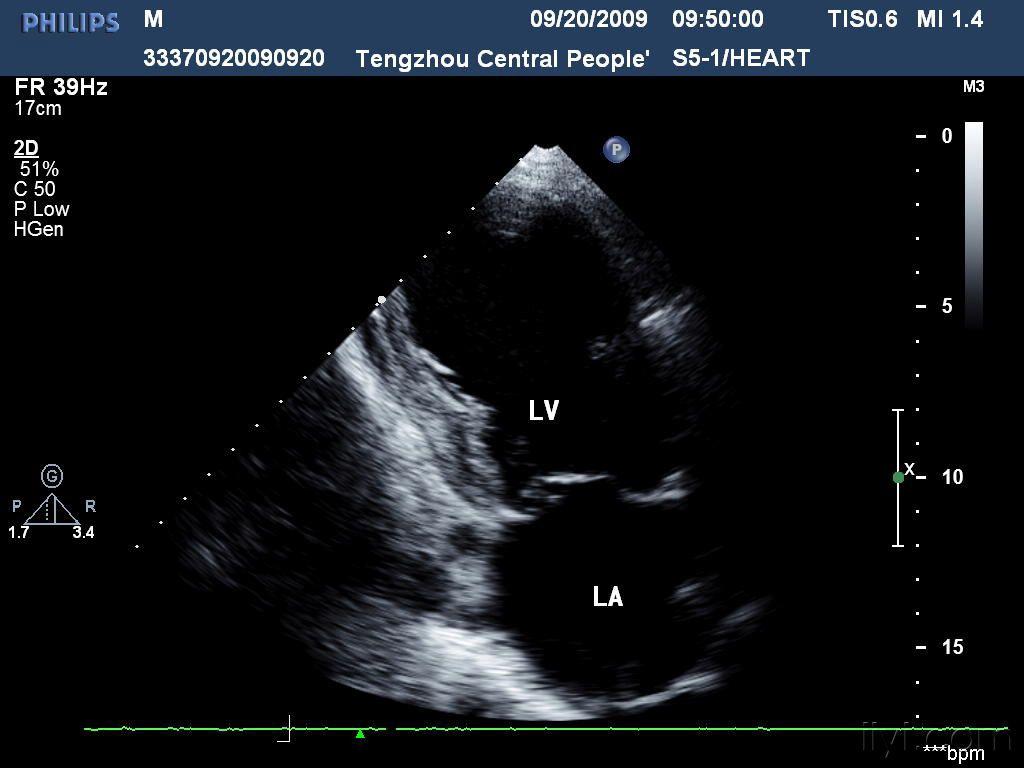

心肌梗死及其并发症的超声诊断

心肌梗塞的超声表现

心脏超声提示广泛前壁心梗

原创华医心诚医生集团专家杨颖:冠心病超声诊断之心梗病例解析